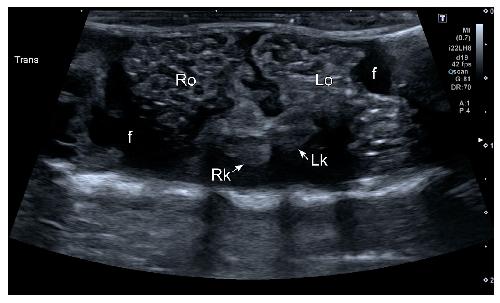

Sex Determination in Two Species of Anuran Amphibians by Magnetic Resonance Imaging and Ultrasound Techniques., Ruiz-Fernández MJ, Jiménez S, Fernández-Valle E, García-Real MI, Castejón D, Moreno N, Ardiaca M, Montesinos A, Ariza S, González-Soriano J., Animals (Basel). November 18, 2020; 10 (11):